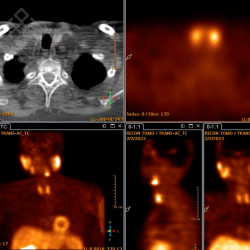

Pour l'injection du traceur radioactif (Sestamibi marqué au Tc99m), le personnel soignant vous posera un cathéter. 15 minutes après l'injection, le manipulateur fera les premières acquisitions dites "précoces" pendant environ 10 minutes. Ensuite, une seconde série d'acquisitions semblable aux images précoces sera réalisée environ 3 heures après l'injection. Une tomoscintigraphie couplée au scanner sera éventuellement réalisée pendant 20 minutes. Le temps d'attente entre les 2 séries d'acquisitions peut se faire en-dehors du service avec un retour à domicile possible ou en salle d'attente.